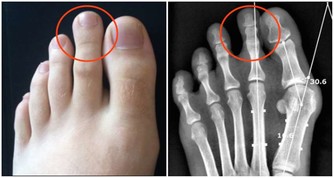

1.水腫,主要顯現在腹部、腿部、腳部和手部。